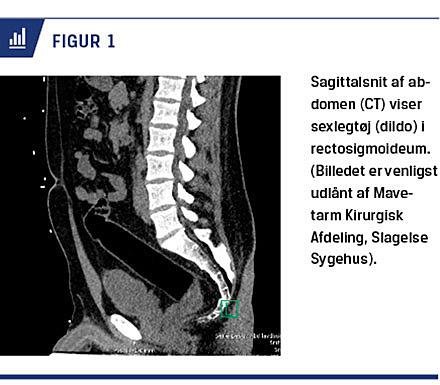

Materialerne, der indføres, varierer i samme omfang som motiverne bag indføring. De hyppigst forekommende fremmedlegemer er sexlegetøj, køkkenredskaber, grøntsager, glasflasker og narko (illegale drug

) [1-5, 14-22]. I Figur 1 ses et eksempel på et fremmedlegeme, der er indført igennem endetarmsåbningen. Størstedelen af fremmedlegemerne indføres i forbindelse med seksuel aktivitet af patienten selv eller partneren, primært som et forsøg på at opnå seksuel tilfredsstillelse gennem stimulering af sensitive områder i rectum [1-3, 18]. Sekundært kan indføring af fremmedlegemer i rectum skyldes underliggende psykiatrisk sygdom. I litteraturen rapporteres der om depression, misbrug af psykoaktive stoffer, særligt alkohol, psykotiske tilstande og personlighedsforstyrrelser som de hyppigste psykiatriske komorbiditeter [1, 2, 5, 7, 8, 11, 12, 20]. Ved personlighedsforstyrrelser, der medfører problemer med affektforvaltning og impulskontrol, er der beskrevet tilfælde, hvor motivet har været at volde skade på den undersøgende læge [3]. I meget sjældne tilfælde er fremmedlegemeindførelse en manifestation af Münchhausens syndrom, suicidal adfærd og selvmutilerende adfærd [1, 9, 11, 12, 21]. Der er i litteraturen beskrevet tilfælde, hvor formålet har været lindring og selvbehandling af anorektale sygdomme og symptomer f.eks. rektalprolaps, forstoppelse, hæmorider og analkløe [3, 5, 12, 22]. Fremmedlegemer kan sluges og ende i rectum, hvilket er beskrevet hos børn, ældre svagtseende og personer med svær mental retardering [2]. Fremmedlegemer kan også være indført i forbindelse med seksuelle overgreb eller vold [1, 3, 6, 11, 12].